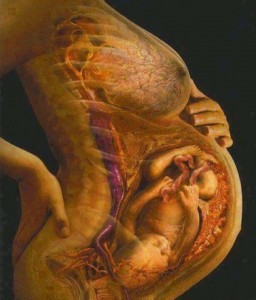

El embarazo es una etapa de la mujer en la que el cuerpo está en constante evolución y movimiento.

Durante el embarazo se secreta una hormona llamada relaxina que responsable de que nuestro cuerpo sea más elástico de lo normal. Esto genera un estrés para la pelvis y el resto del cuerpo, que tendrán que adaptarse al crecimiento del útero. El aumento de peso y consecuente aumento de la curva lumbar, además de los cambios hormonales, desordenes y sobrecargas articulares hacen que esta etapa sea dura. Pueden aparecer molestias y dolores y es importante tratarlo para que no se cronifiquen.